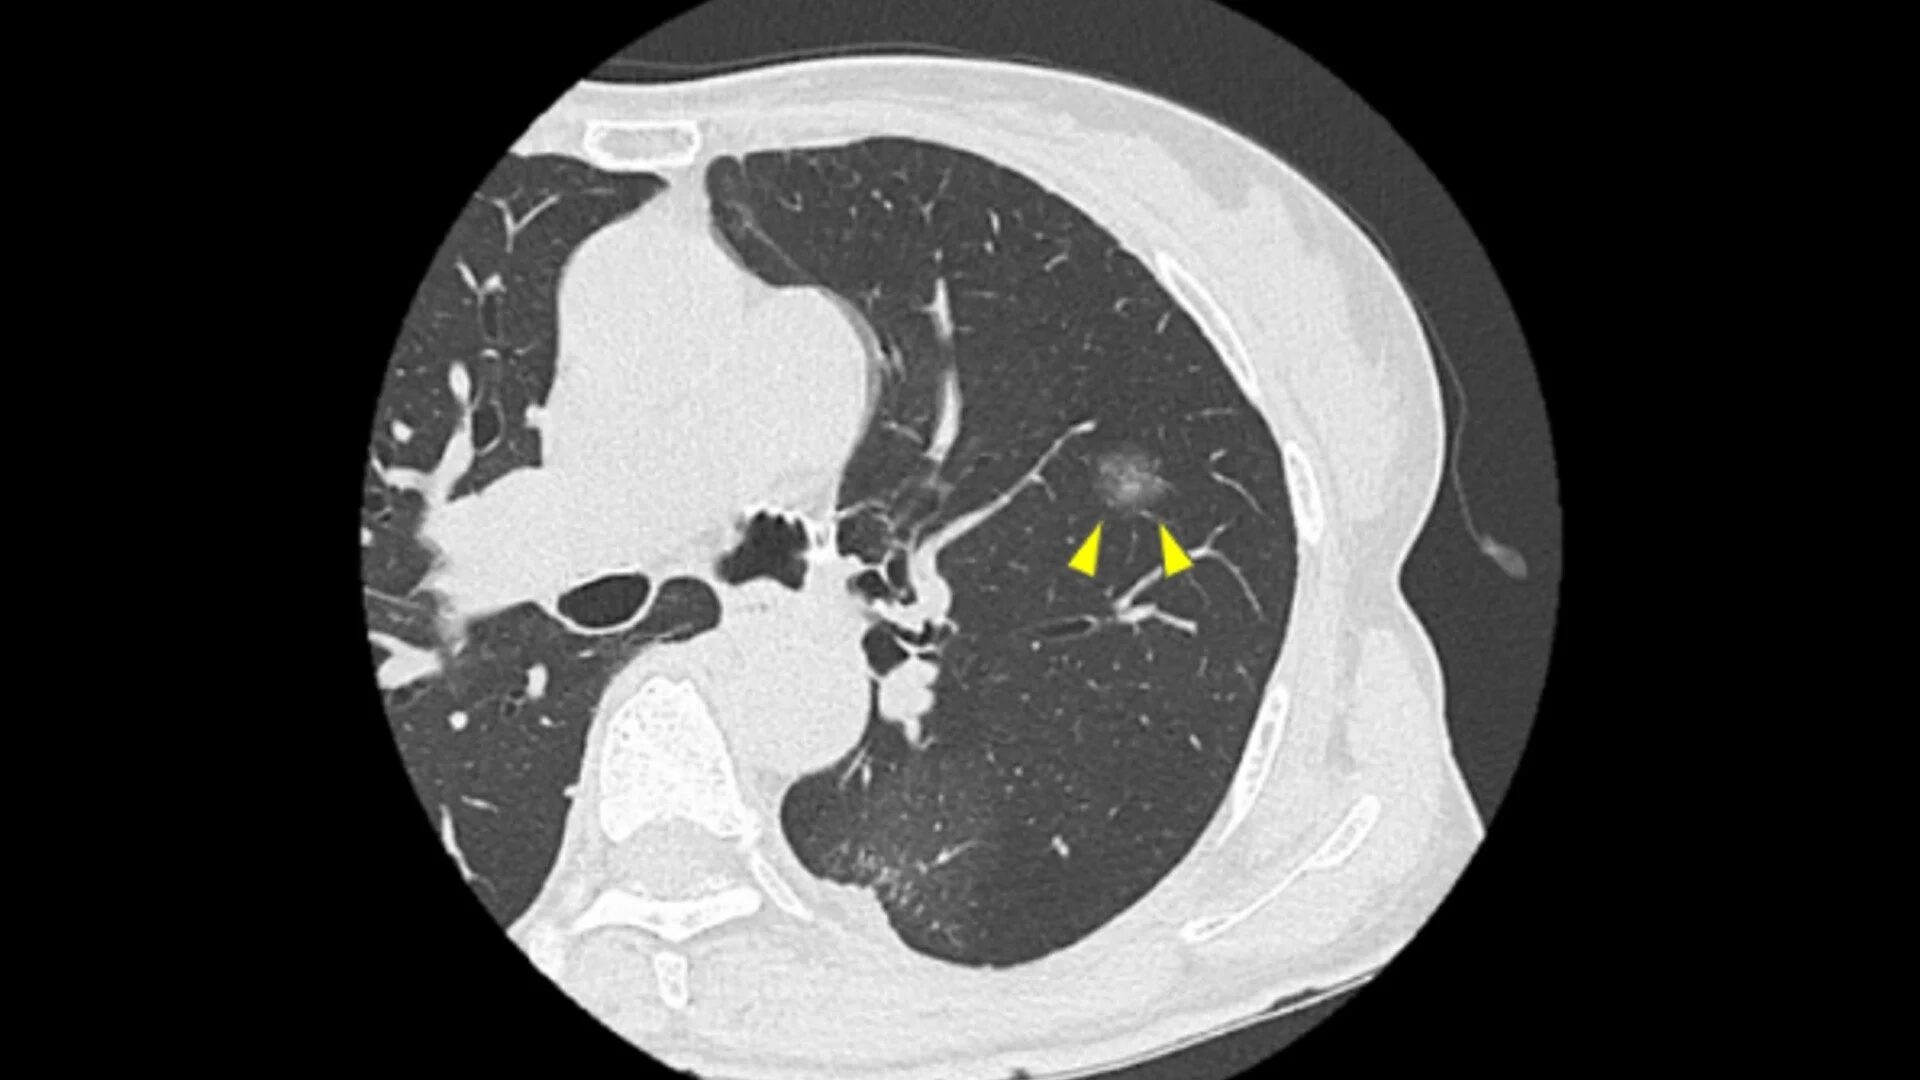

肺に影が見つかった時に最も重要なのは、「それが手術が必要な肺がんらしい影なのか、それとも手術せずに経過観察で良いタイプの影なのか」を、できる限り早く、そして正確に見極めることです。そして、CT画像から手術の必要性を最終的に判断できるのは、やはり「肺がん手術を専門とする呼吸器外科医」です。しかし、多くの患者さんが、そのような専門医にたどり着くまでに長い時間を要しています。

肺に影が見つかった方にとって、治療方針が決まらないまま過ぎてゆく時間は、大きな不安につながります。このクリニックでは、肺がん治療を専門とする呼吸器外科医や麻酔科医を含む4名の専門医が迅速にCT画像を確認し、初診の段階から手術すべきかどうかの提案が可能です。もちろん、その上で経過観察が適切であると判断する場合もありますが、どれだけ小さくても肺に影がある場合、一度は呼吸器外科医に診てもらうことで、手術の機会を逃す可能性は低くなり、患者さんが抱える不安を軽減できるでしょう。